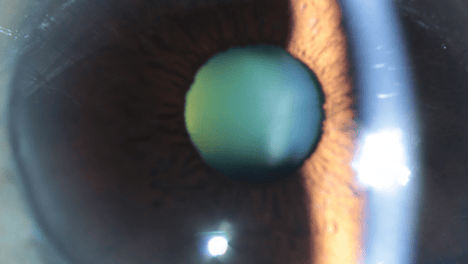

“孤注一掷”的白内障手术,70岁阿姨满意度直冲“1.0”!

在郑州爱尔眼科医院门诊,70岁的白内障患者邓阿姨用暖若春阳的红色锦旗,为一台“孤注一掷”的白内障手术的成功,表达着由衷的感激。某种意义上讲,邓阿姨的手术更显得“孤注一掷”。经过检查,邓阿姨的右眼术后视力达到了…

告别模糊与不便!河南大学附属爱尔眼科精准诊疗,助力40岁+人群重获高清视觉

张女士在医院完成全面检查后,被诊断为高度近视、中度老花合并晶状体浑浊,专家为其制定了“飞秒激光辅助三焦点晶体置换”的手术方案,术后1周,张女士远、中、近视力恢复至1.0,“现在看近看远都清晰,不用再反复摘戴眼…